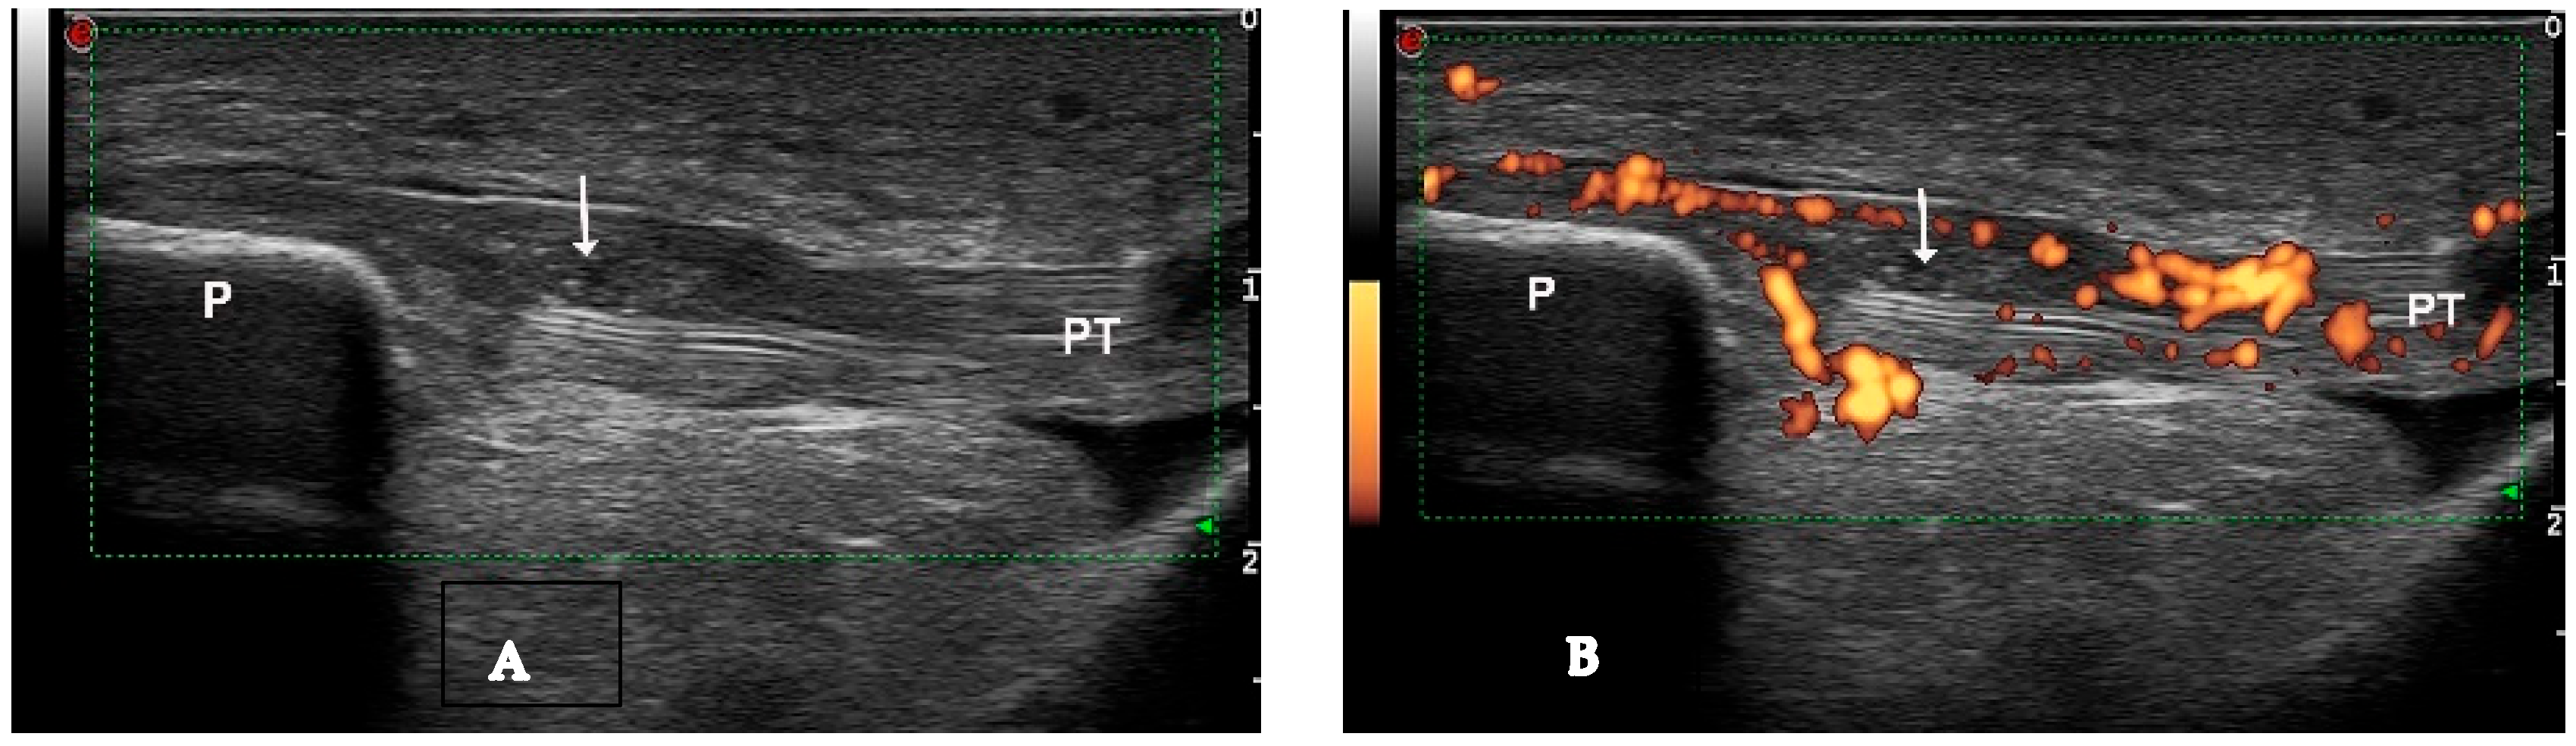

Figure 3.

Intratendinous soft tophus visible in longitudinal view of the proximal insertion of the patellar tendon ((A)—grayscale, (B)—Power Doppler mode). P—patella, PT—patellar tendon, arrow—intratendinous soft tophus.

Figure 4.

Intratendinous hard tophus visible in longitudinal view of the distal insertion of the patellar tendon. Notice the posterior shadowing from the tophus. P—patella, PT—patellar tendon, arrow—intratendinous hard tophus.